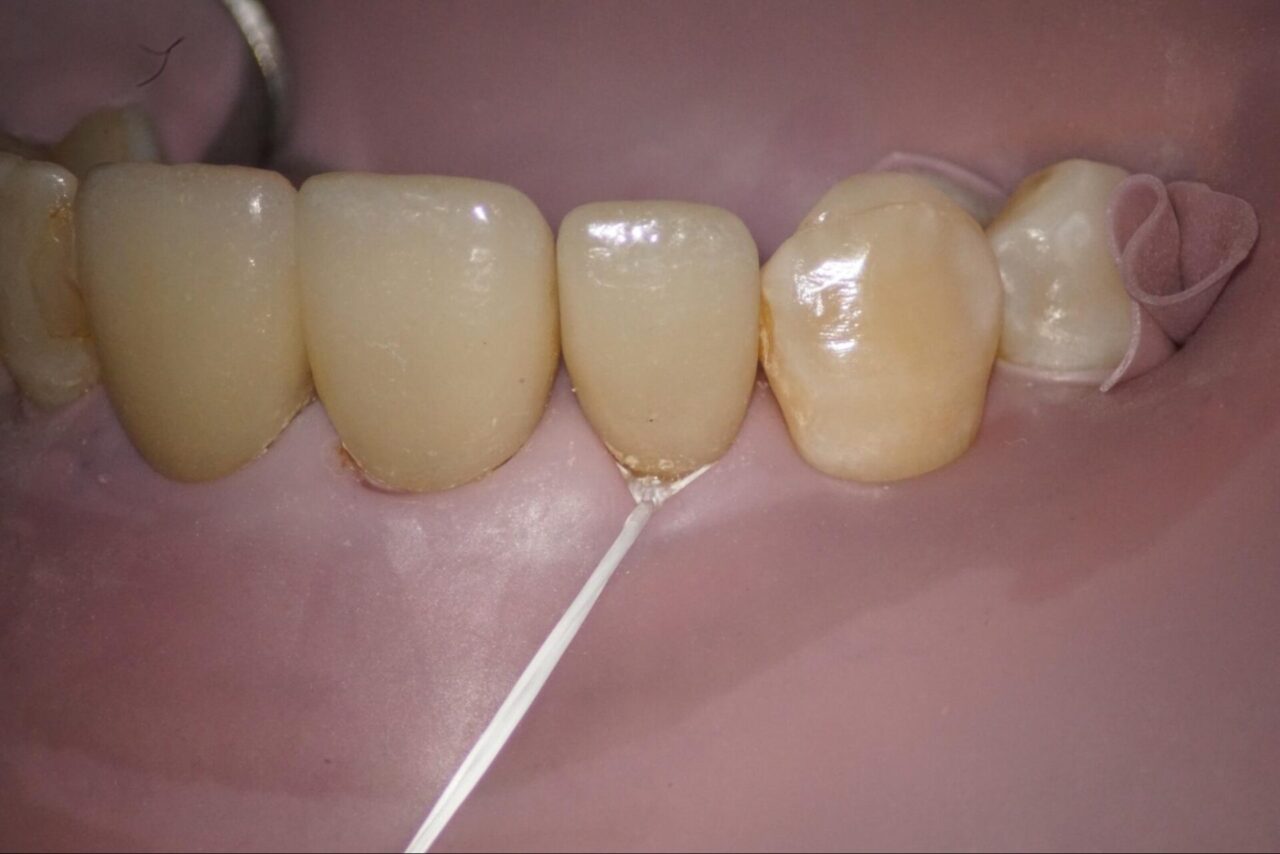

他院で歯根破折を疑われて、当院に来院されました。麻酔後にラバーダム防湿を行い、その後修復物を外します。

可能な限り健全歯質を削らないように細心の注意をはらって以前の修復物を外します。